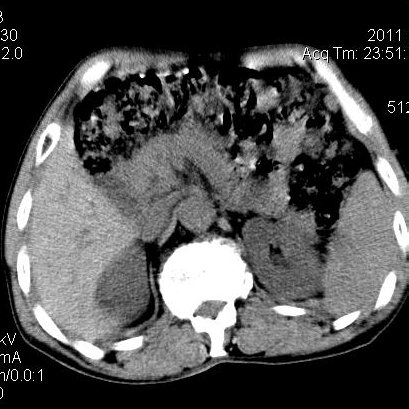

肝左叶发育异常

男性,55岁,骑摩托车摔倒后入院,自述右上腹疼痛

[backcolor=#FF0000]第一次诊断的时候也是这么肯定,可是床旁超声检查并没有发现明显异常,而且患者的一般症状都良好。还好临床只是保守治疗,没有立即手术,第二次复查的时候没有一点变化,又做了MRI检查,没有血肿,

这是一例肝左叶发育异常的,很个性吧~[/backcolor]